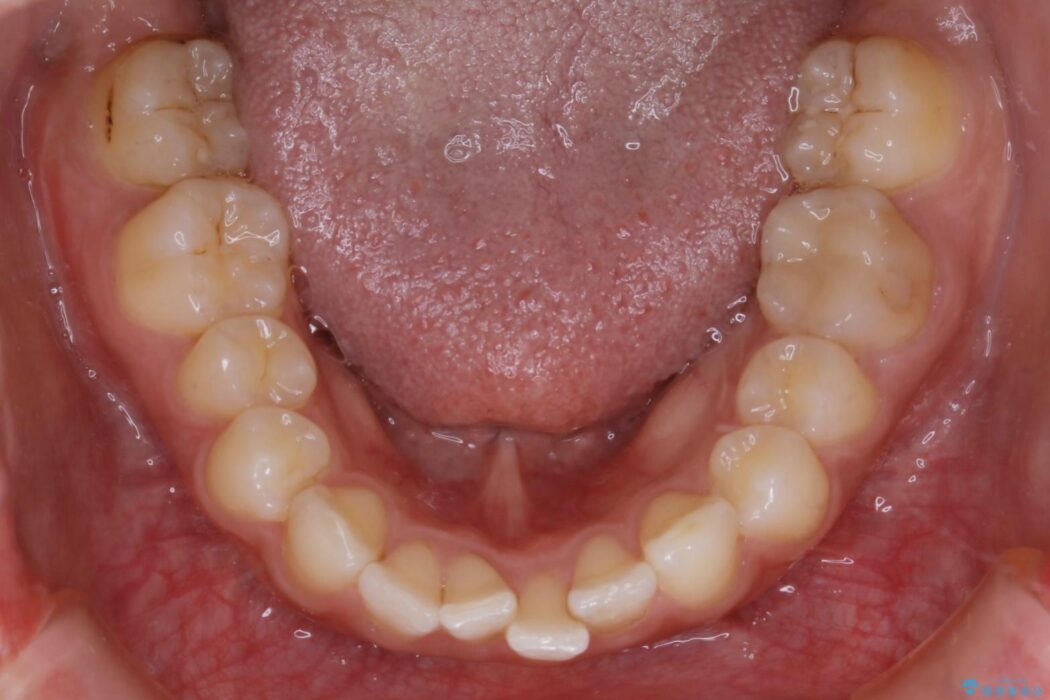

気になるガタツキと噛み合わせを改善したいとご来院されました。

下の歯列よりも上の歯列が前に出ている状態を治すため、マウスピース矯正に加え、患者様にゴムかけのご協力をいただきました。その結果、ガタつきが改善し、上下の噛み合わせが適切な位置で合うようになりました。

歯列弓の拡大

歯並びが悪くなる原因の一つに「歯列弓の狭窄」というものがあります。

奥歯や前歯が内側(舌側)に倒れ込んでしまったり、歯が生えてくる位置が内側になってしまうことにより歯並びのアーチが狭くなってしまうことを言います。

このような場合、歯並びのアーチを拡大してあげるだけでもガタつきを無くすためのスペースがかなり作れることがあります。